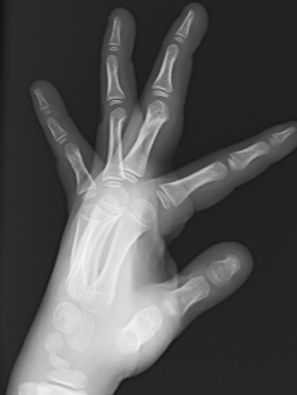

También puede aparecer fracturas de la base de F2, consecuencia de un traumatismo. Dependiendo el tamaño del fragmento, puede aparecer subluxación de la articulación por lo que habrá que realizar una reducción cerrada. La tracción mantenida mediante un fijador externo evita el colapso de la articulación y mantiene la congruencia articular (Figura 21).

Figura 21: a- fractura base F2 intraarticular con subluxación articular y b,c- tratamiento quirúrgico mediante técnica de Suzuki.